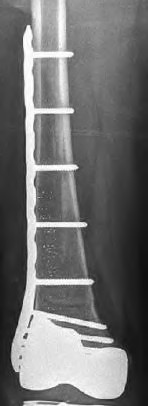

The radiograph demonstrates a periprosthetic femur fracture extending to the tip of the stem. The long spiral fracture is consistent with a loose implant. The bone stock is sufficient. Therefore, this fracture pattern would classify as a B2 using the Vancouver classification system. The Vancouver classification for periprosthetic femoral fractures is simple yet incorporates all the pertinent factors such a location, stem fixation, and bone stock. Type A is a trochanteric fracture- lesser or greater. These can be treated non-operatively usually and ORIF if symptomatic. Type B fractures are around or just below the stem and are subdivided into three types. Type B1 is a fracture with a well fixed stem.

The treatment is cable plating or allograft struts or a combination of the two. Type B2 is a fracture with a loose stem with good bone stock. The treatment is a cementless porous coated long stem atleast two diameter length past the

fracture site. Type B3 is a fracture with a loose stem and comminution. For younger patients, use cementless porous coated long stems with allograft struts. For older patients, consider a tumor prosthesis. Cement fixation is sometimes necessary Type C is a fracture well below the stem tip. These can be treated independently of the prosthesis.

Figure A shows a lytic lesion of the proximal femur with an intramedullary implant. Figure B shows a proximal femoral replacement.